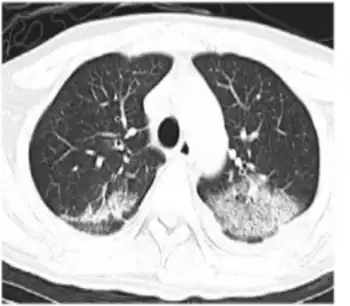

HHV-6 pneumonitis- CT scan on shows reticulation, ground-glass opacity, consolidation, and peripheral lung sparing in bilateral lung fields[46]

The classical presentation of primary HHV-6b infection is as exanthema subitum (ES) or "roseola", featuring a high temperature followed by a rash. However, one study (1997) indicated that a rash is not a distinguishing feature of HHV-6 infection, with rates similar to non-HHV-6 infections (10–20% of febrile children in both groups). HHV-6 infections more frequently present with high temperatures (over 40C), at a rate of around two thirds compared to less than half in the non-HHV-6 patients. Similarly significant differences were seen in malaise, irritability, and tympanic membrane inflammation.[13]